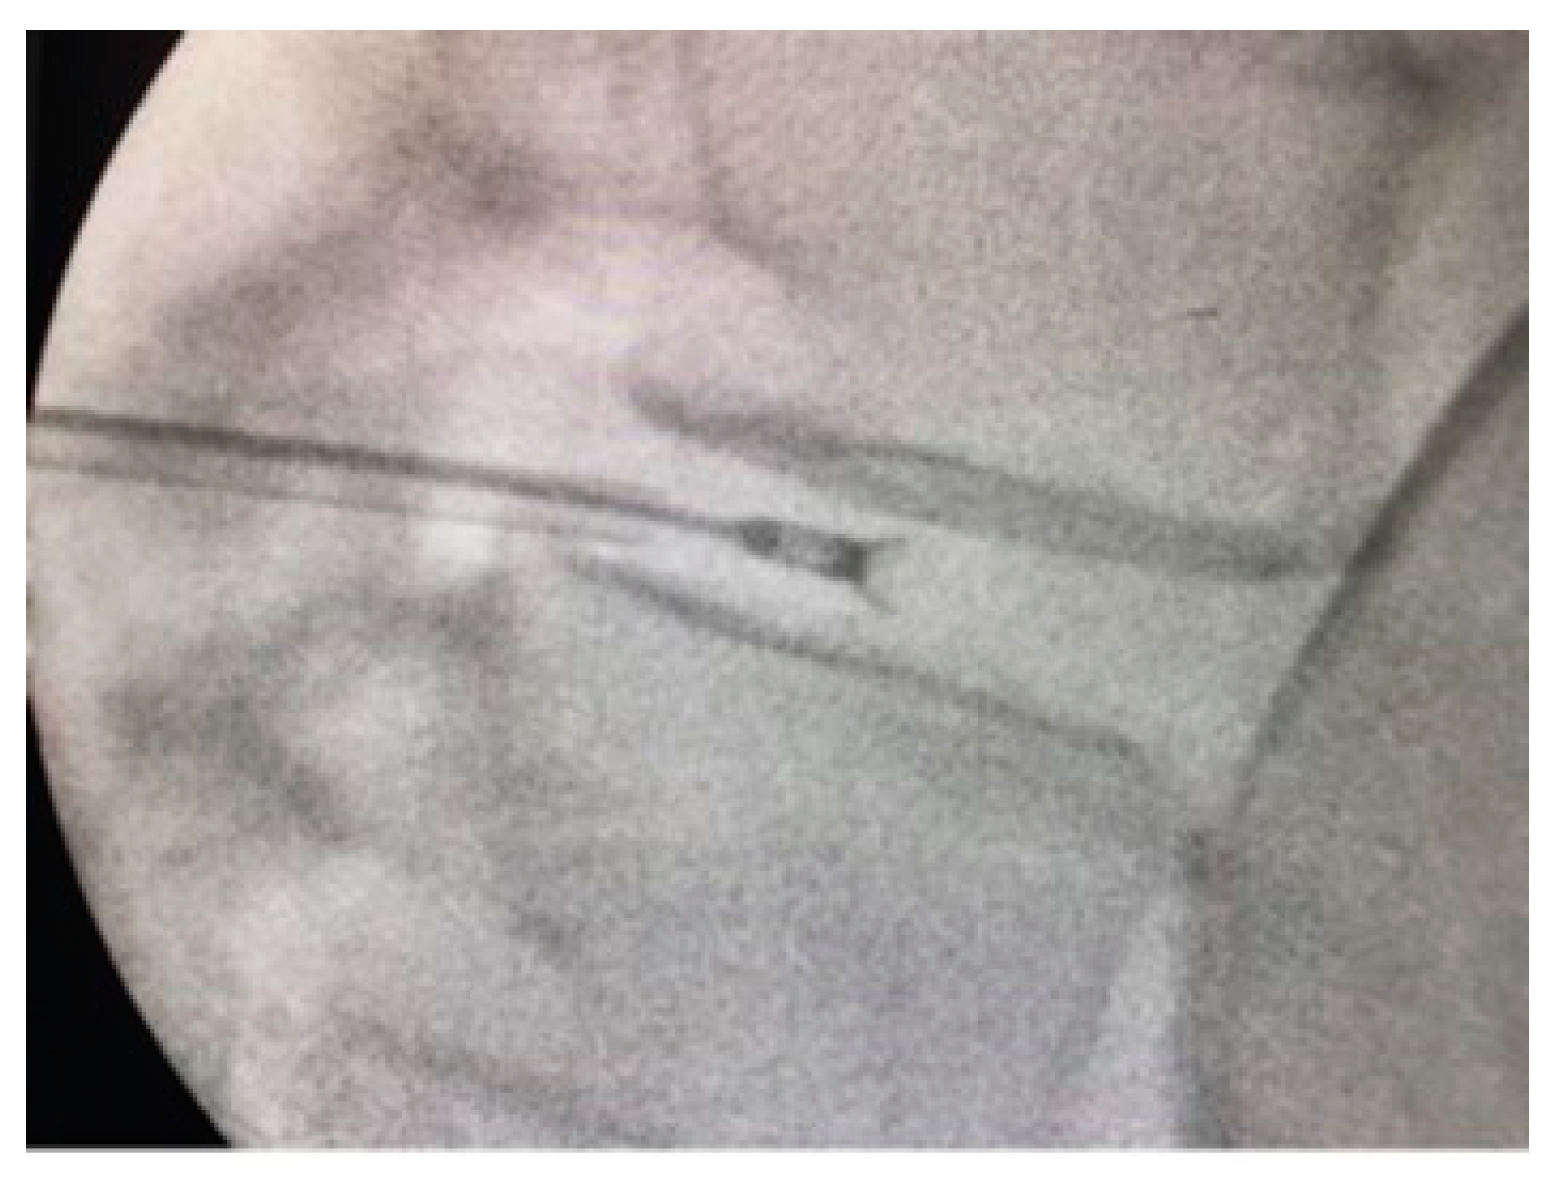

2.3. Intervention and Follow-Up